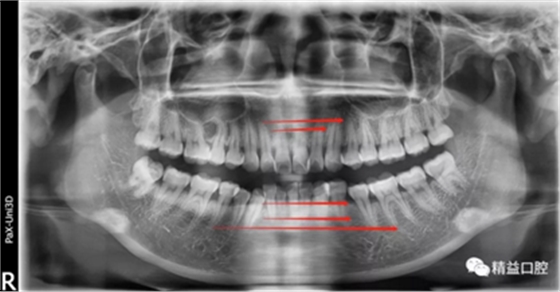

嘴唇突度非常明顯,后期經(jīng)過測量,發(fā)現(xiàn)是典型的安氏II類加骨性II類,齙牙前突。

李醫(yī)生考慮到俊上下門牙吸收嚴重,前牙突度大,建議先拔除上頜兩顆四,對上牙進行內(nèi)收,后期看矯正效果再對下牙進行處理。

為了保證矯正效果和整體牙齒健康,李醫(yī)生在矯正過程中不斷根據(jù)每次牙齒移動的情況,對所施加的矯正力以及每次復(fù)診的時間進行精細的調(diào)整,在放慢矯正速度的同時,以更加輕柔的力量來拉動牙齒移動。事實證明一切OK,上牙的內(nèi)收效果非常的好。